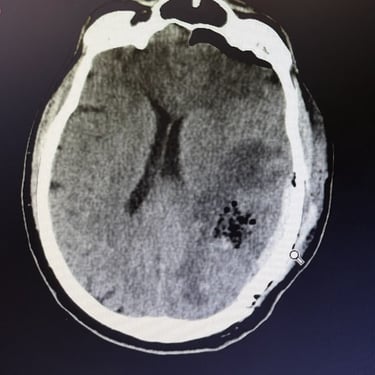

🧠Hematoma intracerebral parietal: tratamiento mediante craneotomía con evacuación de hemorragia.

El hematoma intracerebral parietal es una emergencia neurológica asociada a alta morbimortalidad. La craneotomía con evacuación del hematoma es una intervención quirúrgica indicada en casos seleccionados para reducir la presión intracraneal, limitar el daño cerebral y mejorar el pronóstico funcional en pacientes con deterioro neurológico significativo.